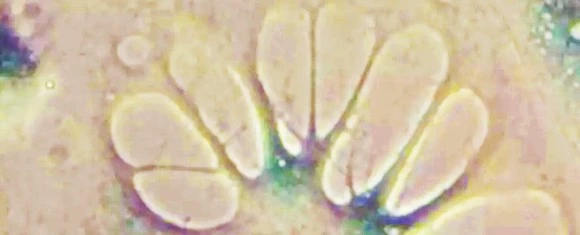

993B32385B777AF215

<인간 세포에 일어난 노화 세포>